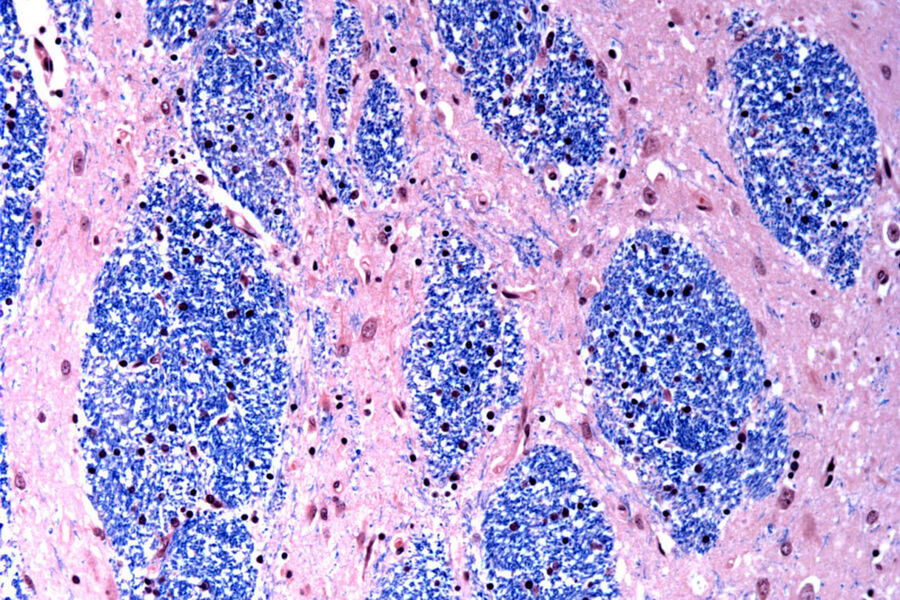

В новом исследовании ученые изучили мозговую ткань, пожертвованную 53 пациентами с болезнью Гентингтона, и 50 здоровыми людьми.

Специалисты сосредоточились на мутации Гентингтона, которая включает в себя участок ДНК в определенном гене, где трехбуквенная последовательность — CAG — повторяется по крайней мере 40 раз.

У людей без этого заболевания эта последовательность повторяется всего от 15 до 35 раз. Ученые обнаружили, что тракты ДНК с 40 или более такими «повторами» со временем расширяются, пока не станут длиной в сотни CAG. Как только CAG достигают порогового значения около 150, определенные типы нейронов начинают отмирать.